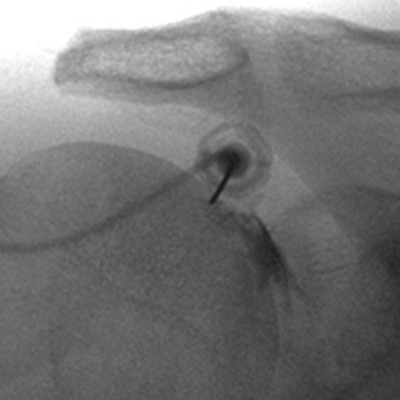

Infiltration sous guidage radioscopique

Lorsque l’on souhaite traiter une zone plus profonde, un guidage radioscopique peut être nécessaire.

Ceci est notamment le cas des infiltrations articulaires périphériques (épaule, genou, coude, cheville, hanche…).

Il est possible de combiner l’examen à un arthroscanner, si un bilan lésionnel approfondi est nécessaire.